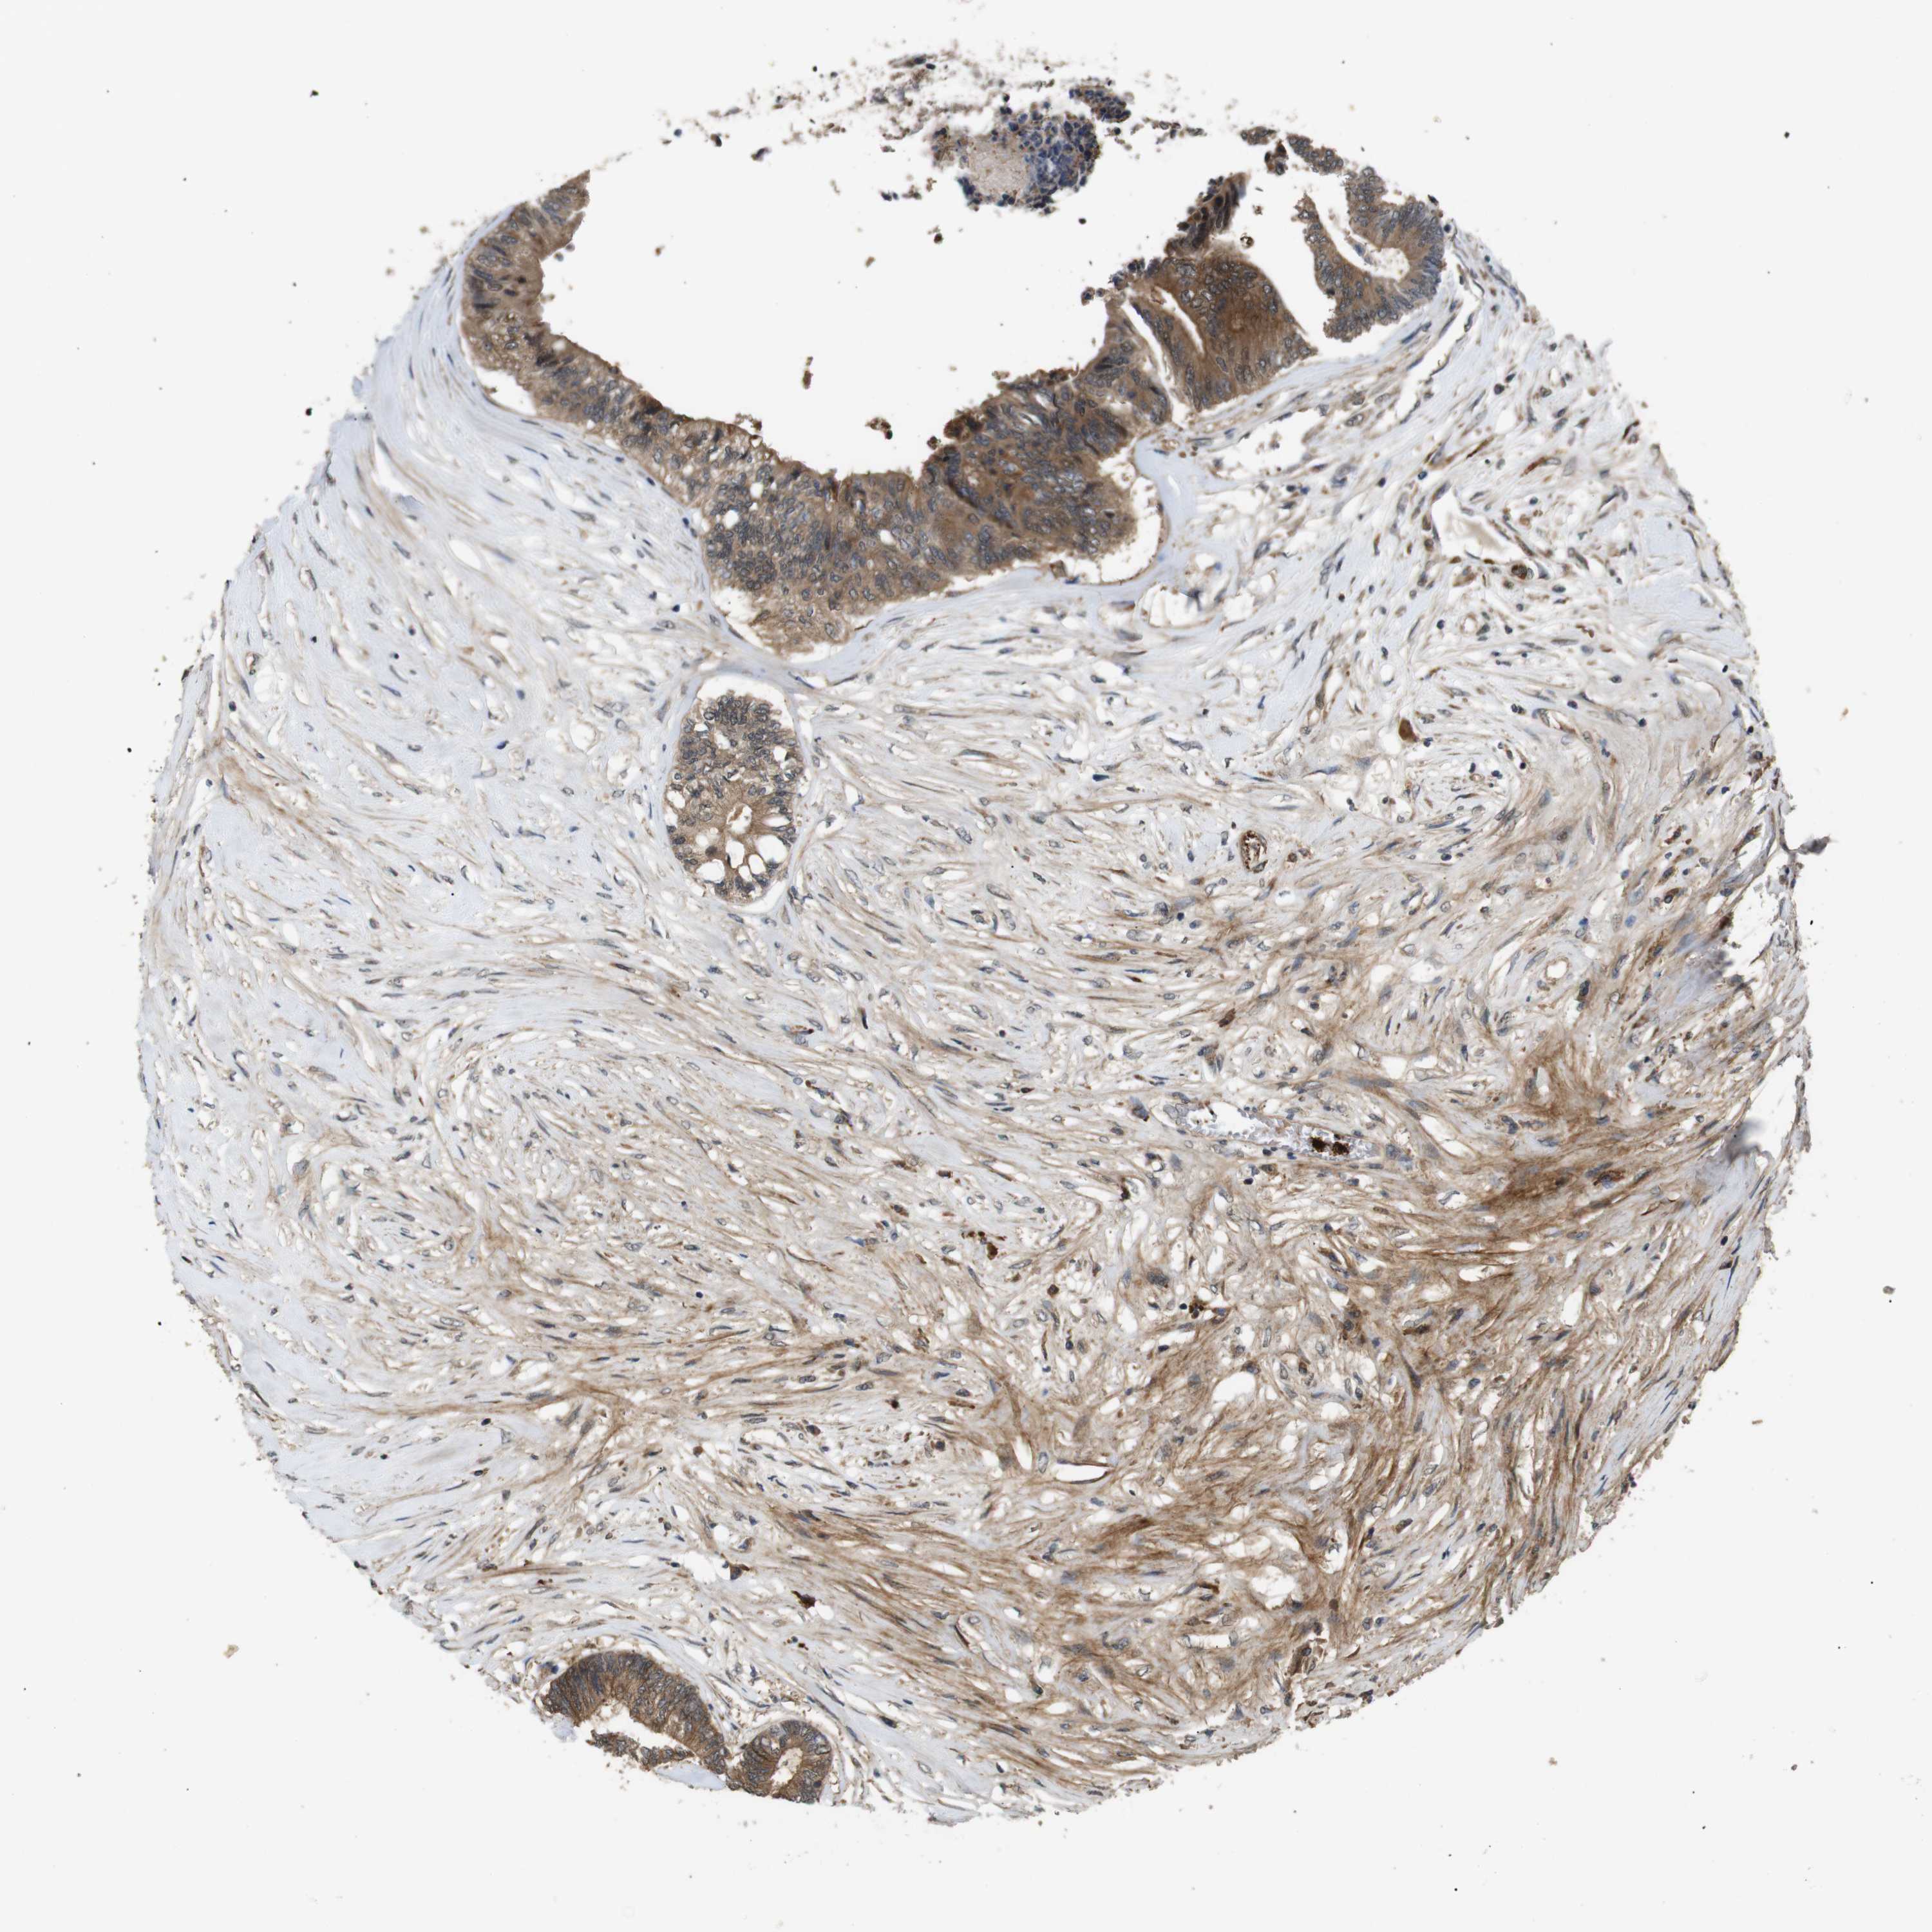

CANCER COLORECTAL CANCER Show tissue menu

Colorectal cancer

Human cancer

Colon adenocarcinoma

Rectum adenocarcinoma